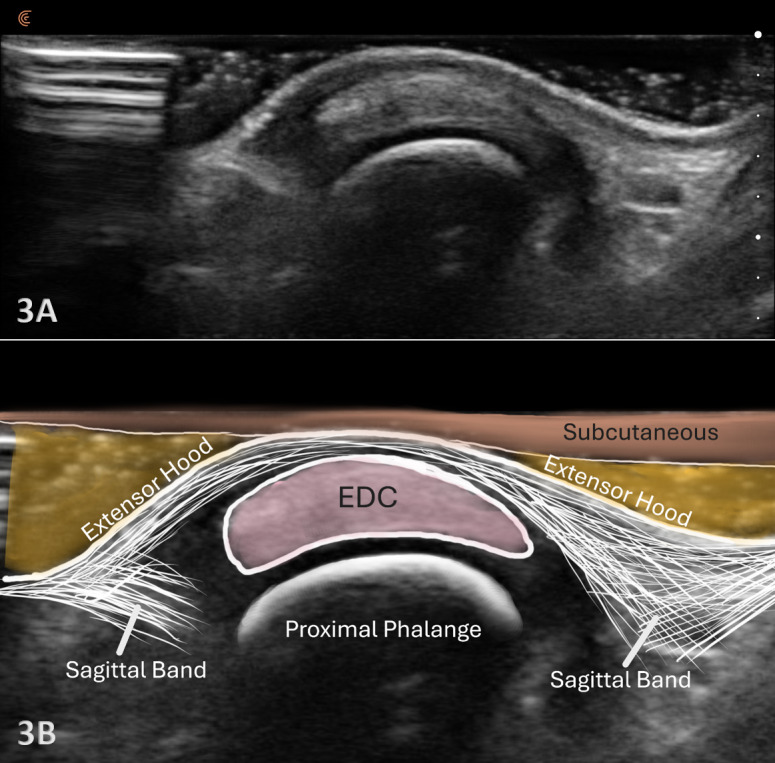

Injuries to the hand and fingers are among the most common injuries in orthopedics and general practice, as they are the part of the human body that interacts most frequently with our environment. Diagnostic musculoskeletal (MSK) ultrasound offers a portable, real-time, and cost-effective alternative that is very useful for obtaining information about small structures like the finger extensor tendons. MSK ultrasound is adept at detecting changes in both tendon tissue composition and integrity. This manuscript will review the utility of MSK ultrasound in evaluating finger extensor tendons and include a review of its anatomy, common injury patterns, sonographic techniques, and clinical implications for professional rehabilitation. By integrating MSK ultrasound into clinical practice, providers can improve the accuracy of diagnosis, enhance diagnostic confidence, monitor healing progression, and guide rehabilitation strategies to optimal patient outcomes.